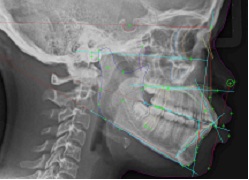

Records taking, Diagnosis, Treatment Plan, Classification and Fee.

In this phase Cephalometric X-Rays(above), Panoramic X-Rays(below), Orthodontic Photos(Interoral and Extraoral) and Impression(Molds) are made and taken for study purposes.